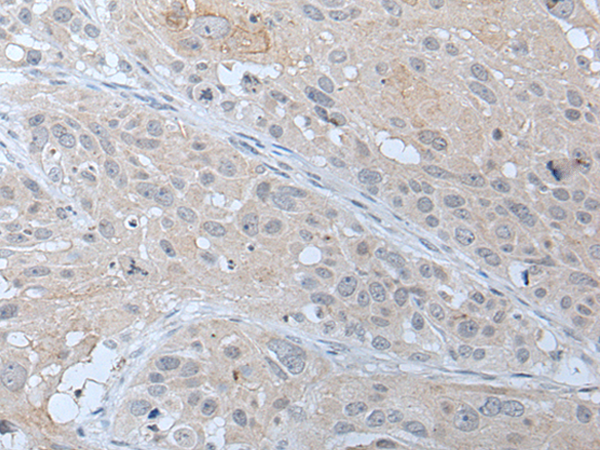

分类: 科研抗体货号: P12773别名:应用: WB反应种属: Human